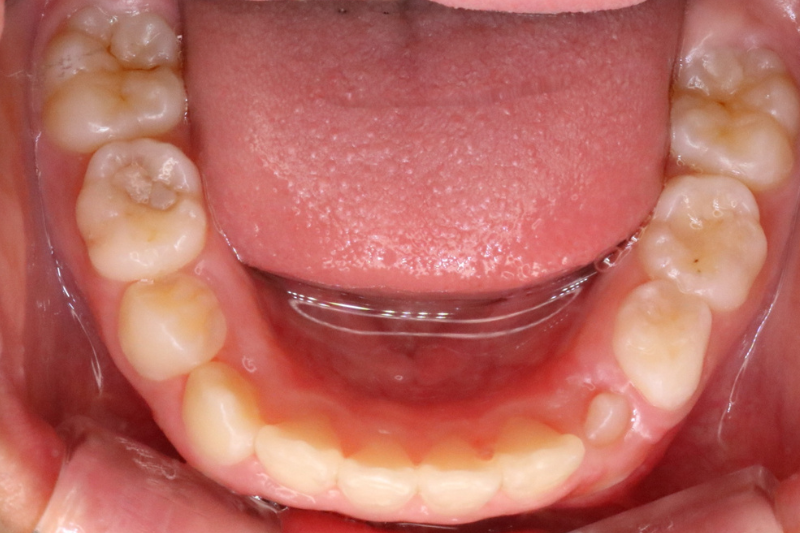

Before

症例3 治療前

After

症例3 治療後

年齢・性別 10歳・女の子

治療内容 インビザラインファースト

治療期間 2年2ヶ月

費用 400,000円(税込)

主なリスク 矯正装置の装着時に違和感や痛みが生じる場合があります。

装置の使用状況により治療期間が延長する場合があります。

治療後、保定装置を使用しない場合は後戻りする可能性があります。

治療結果には個人差があります。